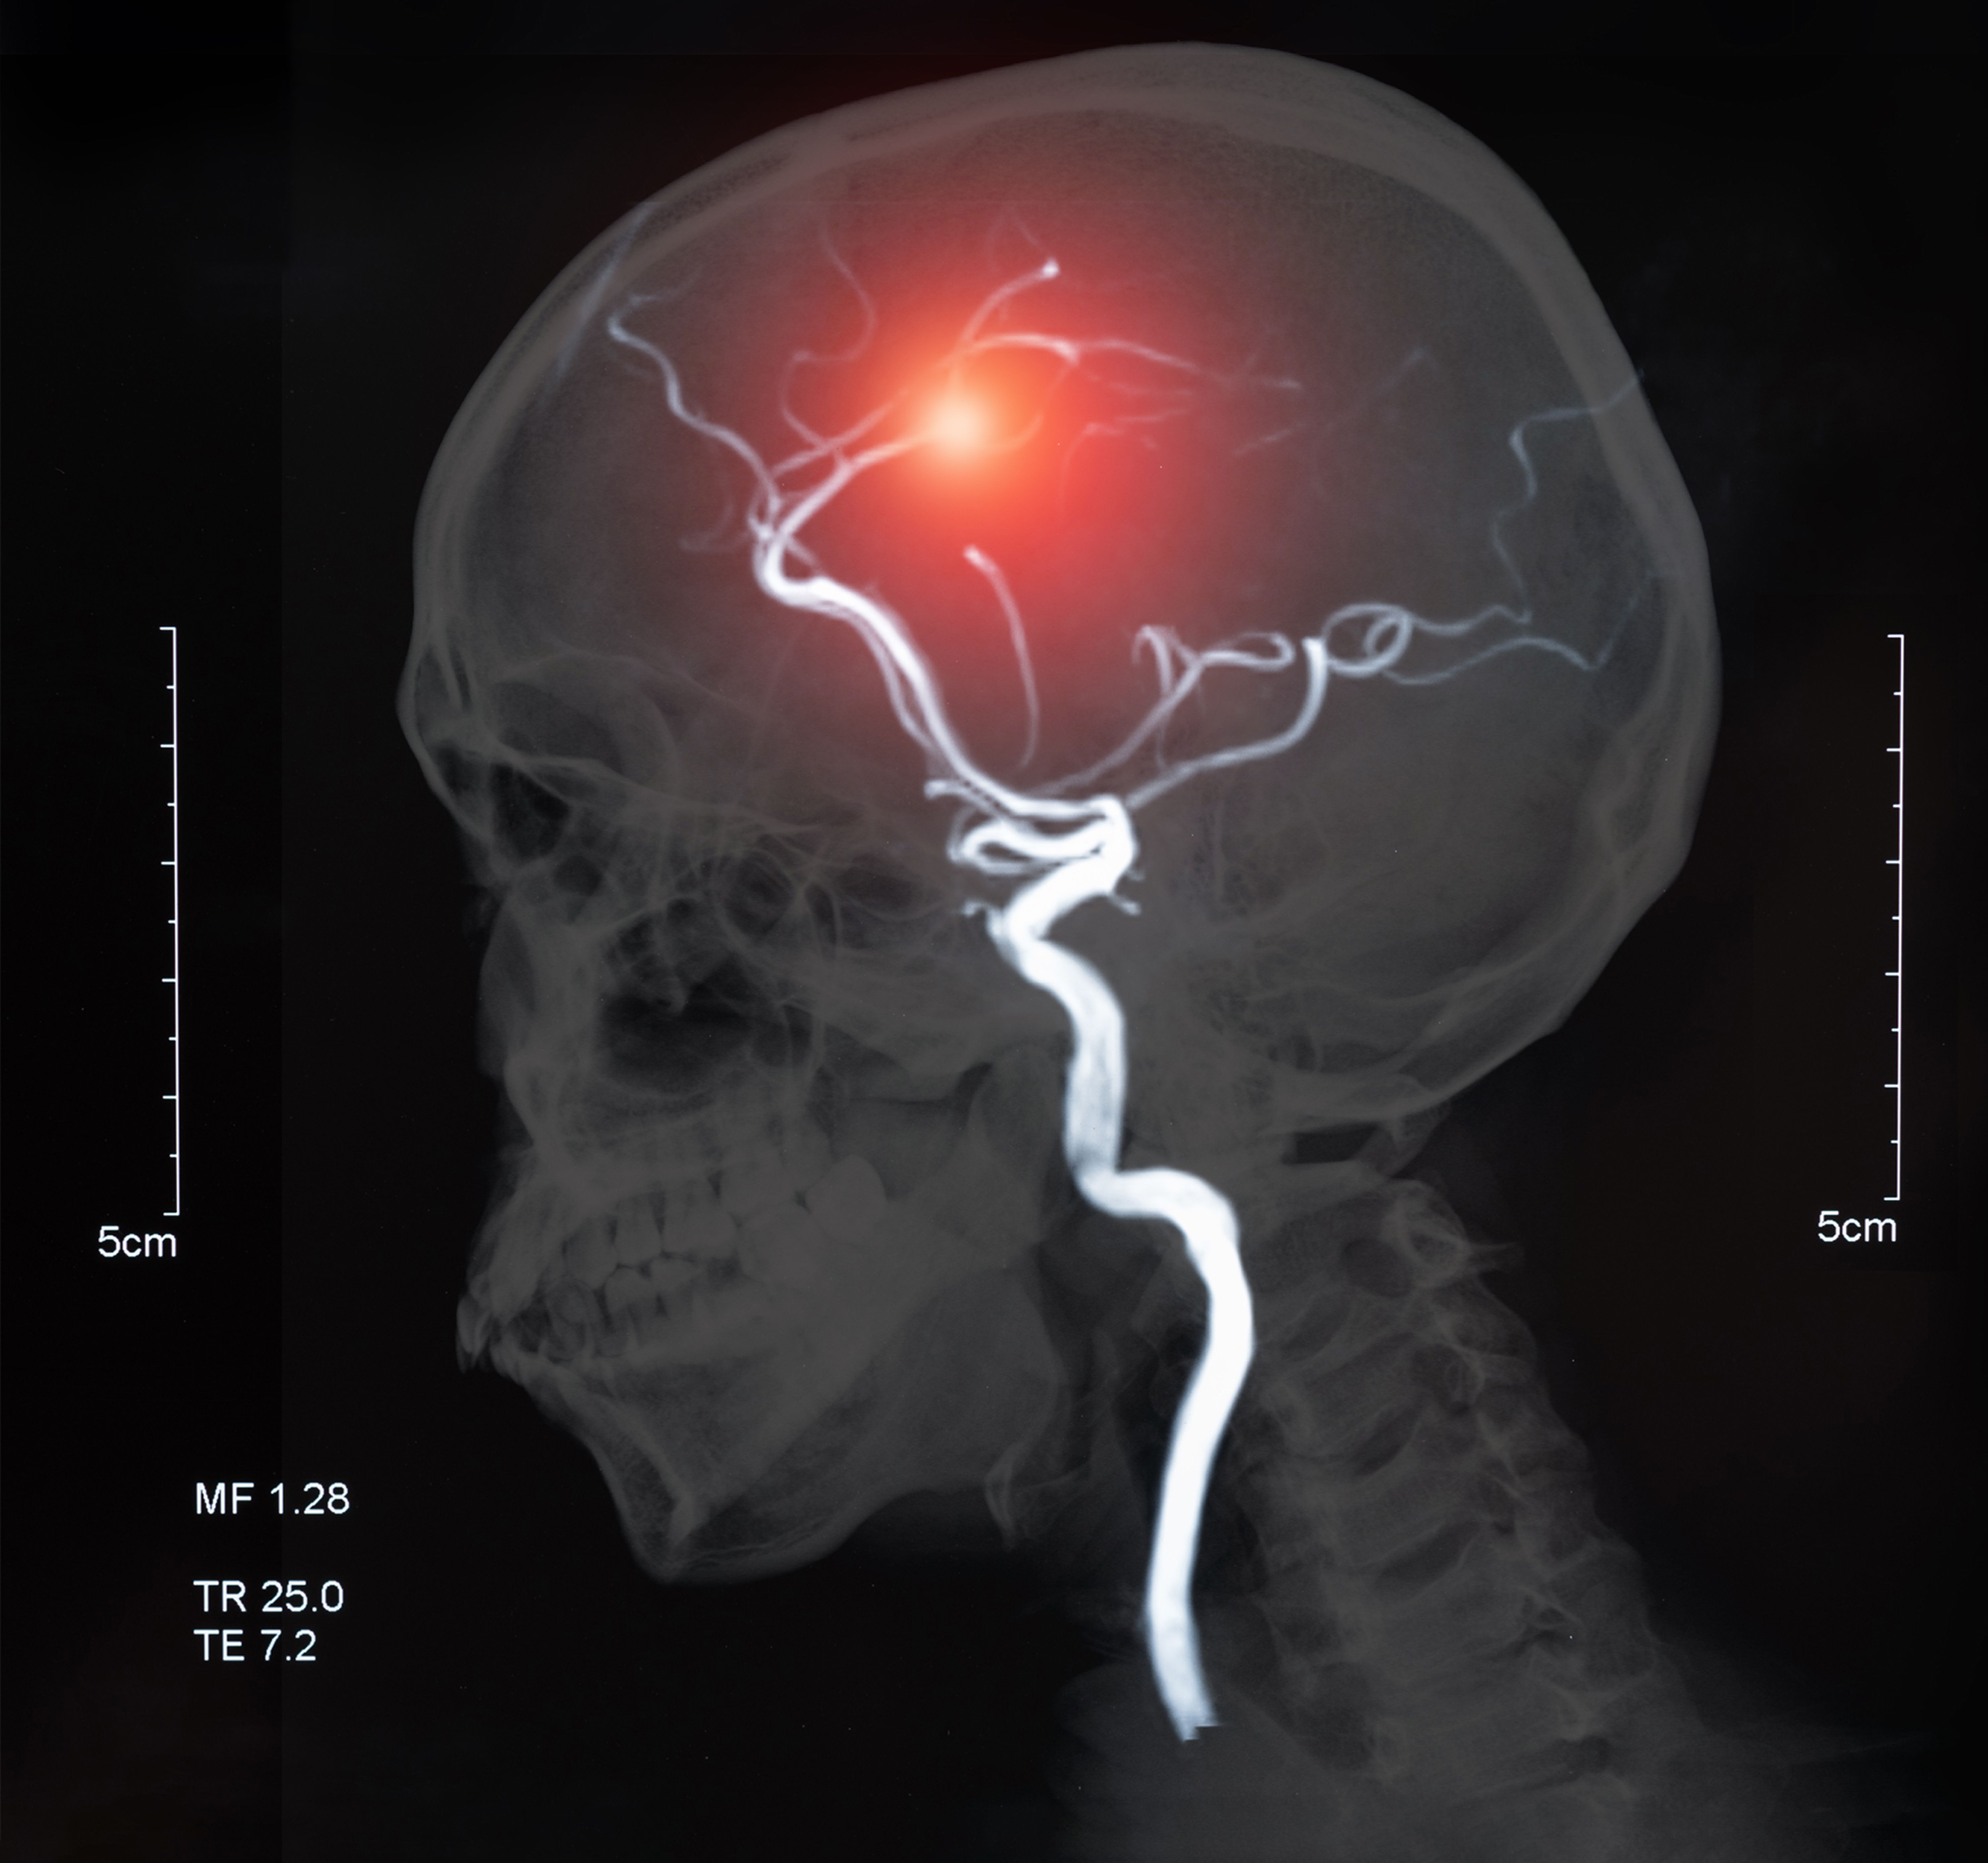

The risks of stroke and heart attack are increased by certain hormonal contraceptives, according to a recent study published in The BMJ.1

The study found increased risks from multiple forms of hormonal contraceptives, but the most significant risks were from oestrogen products. Researchers noted that the absolute risks remain low overall.